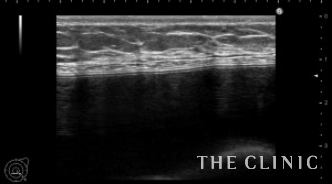

エコー所見です。左はバッグの破損はありません。

右はバッグが破損し、鎖骨近くまで被膜内にシリコンが漏れていました。